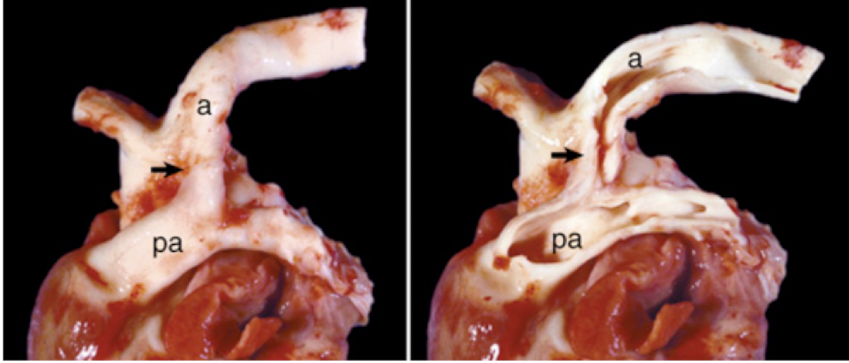

<p>What is this showing?</p>

What is this showing?

patent ductus arteriosus